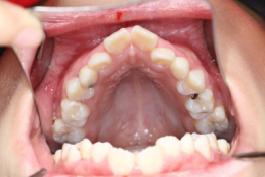

❸ 牙齿不齐:影响咬合关系,影响美观。

前

后